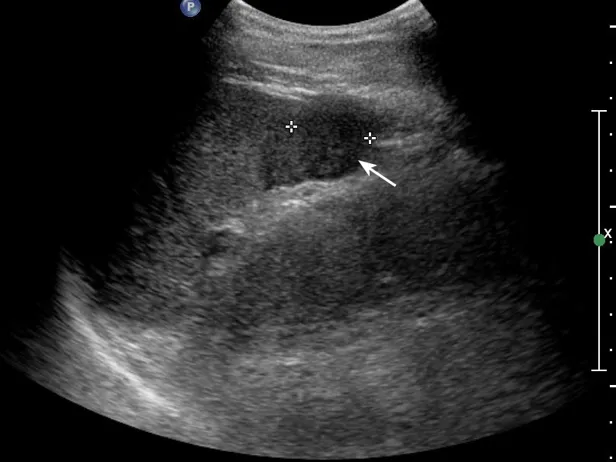

灰阶超声,脾破裂,显示脾实质内见低回声不均匀区,边界不规则(箭头所示) 。